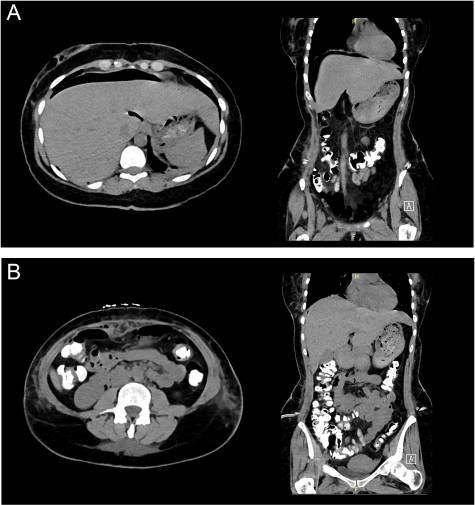

就胸部X光片中的发现咨询了普外科团队,经过评估,进行了紧急腹部计算机断层扫描(CT),并进行了静脉、口腔和直肠造影(图2A和B),显示有中度气腹和腹膜外皮下积气。然而,造影剂可以自由通过,没有泄漏或外渗的迹象。

图2(A) 腹部CT显示膈下气腹。(B) 腹部CT三重造影,无任何造影剂外渗